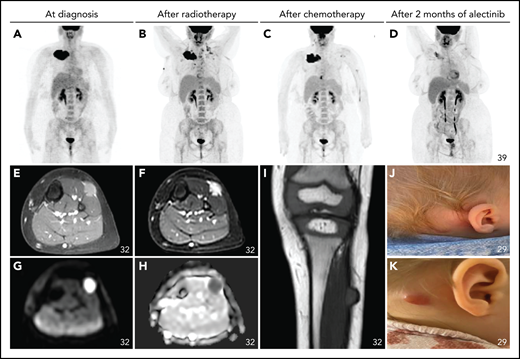

Nonneurologic disease manifestations in ALK-positive histiocytosis patients with single-system disease (Group 2). (A-D) Successive fluorodeoxyglucose PET-CT images of an adult female with a large right clavicular tumor at diagnosis (A; time, 0) and after treatment with radiotherapy (B; time, 5.5 months), 6 weeks of vinblastine/prednisone-based chemotherapy (C; time, 9.5 months), and 2 months of alectinib (D; time, 14 months). (E-I) T1-weighted contrast-enhanced (E), T2-weighted (F), diffusion-weighted (G), apparent diffusion coefficient (H), and plain T1-weighted (I) MRI images of the left lower leg of a child at diagnosis showing a single soft tissue tumor that infiltrates the musculature and shows contrast enhancement and restricted diffusion. (J-K) Photographs of the retroauricular scalp lesion of an infant, with a clear change in clinical appearance after 3 months (K).

Patients in Group 2 were 20 children and 3 adults, including 12 cases with neurologic involvement (52%). Patients with neurologic involvement presented with diverse neurological symptoms, including seizures (3/12), ataxia (3/12), headaches (3/12), vomiting (2/12), hypotonicity (2/12), unclear paroxysmal neurologic symptoms (“spells”) (1/12), torticollis (1/12), trigeminal neuralgia (1/12), paresis (1/12), and diplopia (1/12). Tumoral lesions were widely distributed in the central and peripheral nervous system (Figure 4J-S; Table 3). In addition, 2 patients had cerebrospinal fluid monocytosis, including 1 case with a very low level of ALK rearrangements in the cerebrospinal fluid by FISH analysis. The 11 patients with nonneurologic disease comprised 1 case with a single lung tumor, 2 cases with solitary bone lesions, and 8 children with localized skin lesions or soft tissue tumors in varying locations (Figure 5; Table 3).

First-line treatment consisted of surgical resection in 13/23, radiation in 1/23, conventional systemic therapy with or without local therapy in 4/23, and ALK inhibition in 1/23 patients (Table 2). Furthermore, 1/23 patients was observed without treatment, 1/23 was not treated yet, and 2/23 were lost to follow-up. Of those with local therapy, 2/14 had progressive disease. Of patients treated with conventional systemic therapy, 3/4 had an objective response, and 1/4 had progressive disease. The patient treated with ALK inhibition had an objective response. Second-line treatment was given to 4 patients. ALK inhibition was administered in 2/4 patients with objective response, whereas the 2 others received chemotherapy with progressive disease. Third-line treatment with ALK inhibition was initiated in 1 of these patients with objective response (Figure 5A-D). Responses to ALK inhibition were durable in 4/4 patients (Figure 7).